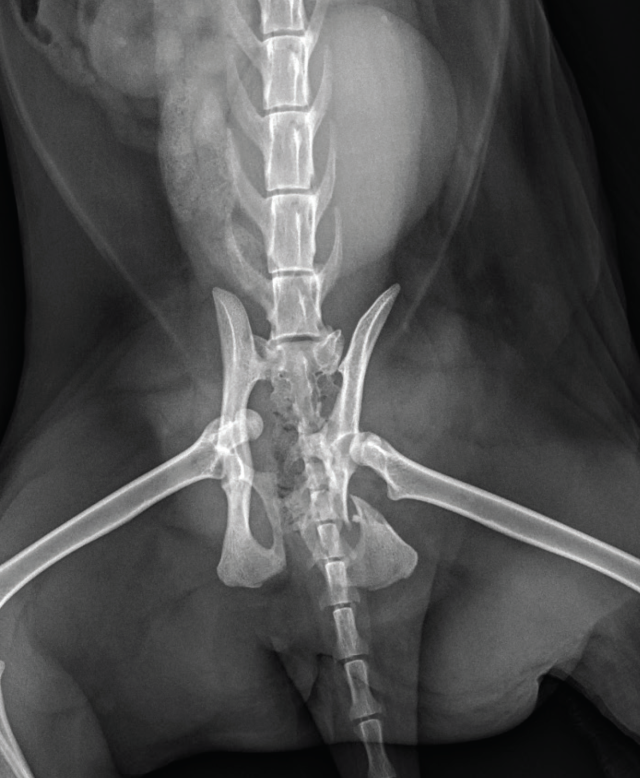

Pelvic trauma is a common finding in feline blunt-trauma patients and survey radiographs are recommended, even in ambulatory cats (Figure 9). Crepitus on manipulation of the pelvic limbs or palpation of fractures directly via rectal examination can provide an initial indication. Sacroiliac, coxofemoral and distal joint luxations, as well as long bone fractures are also fairly common and may be evident on physical examination or can be assessed on survey radiographs. The abdomen should also be carefully palpated for subtler abdominal wall ruptures (Figure 10).